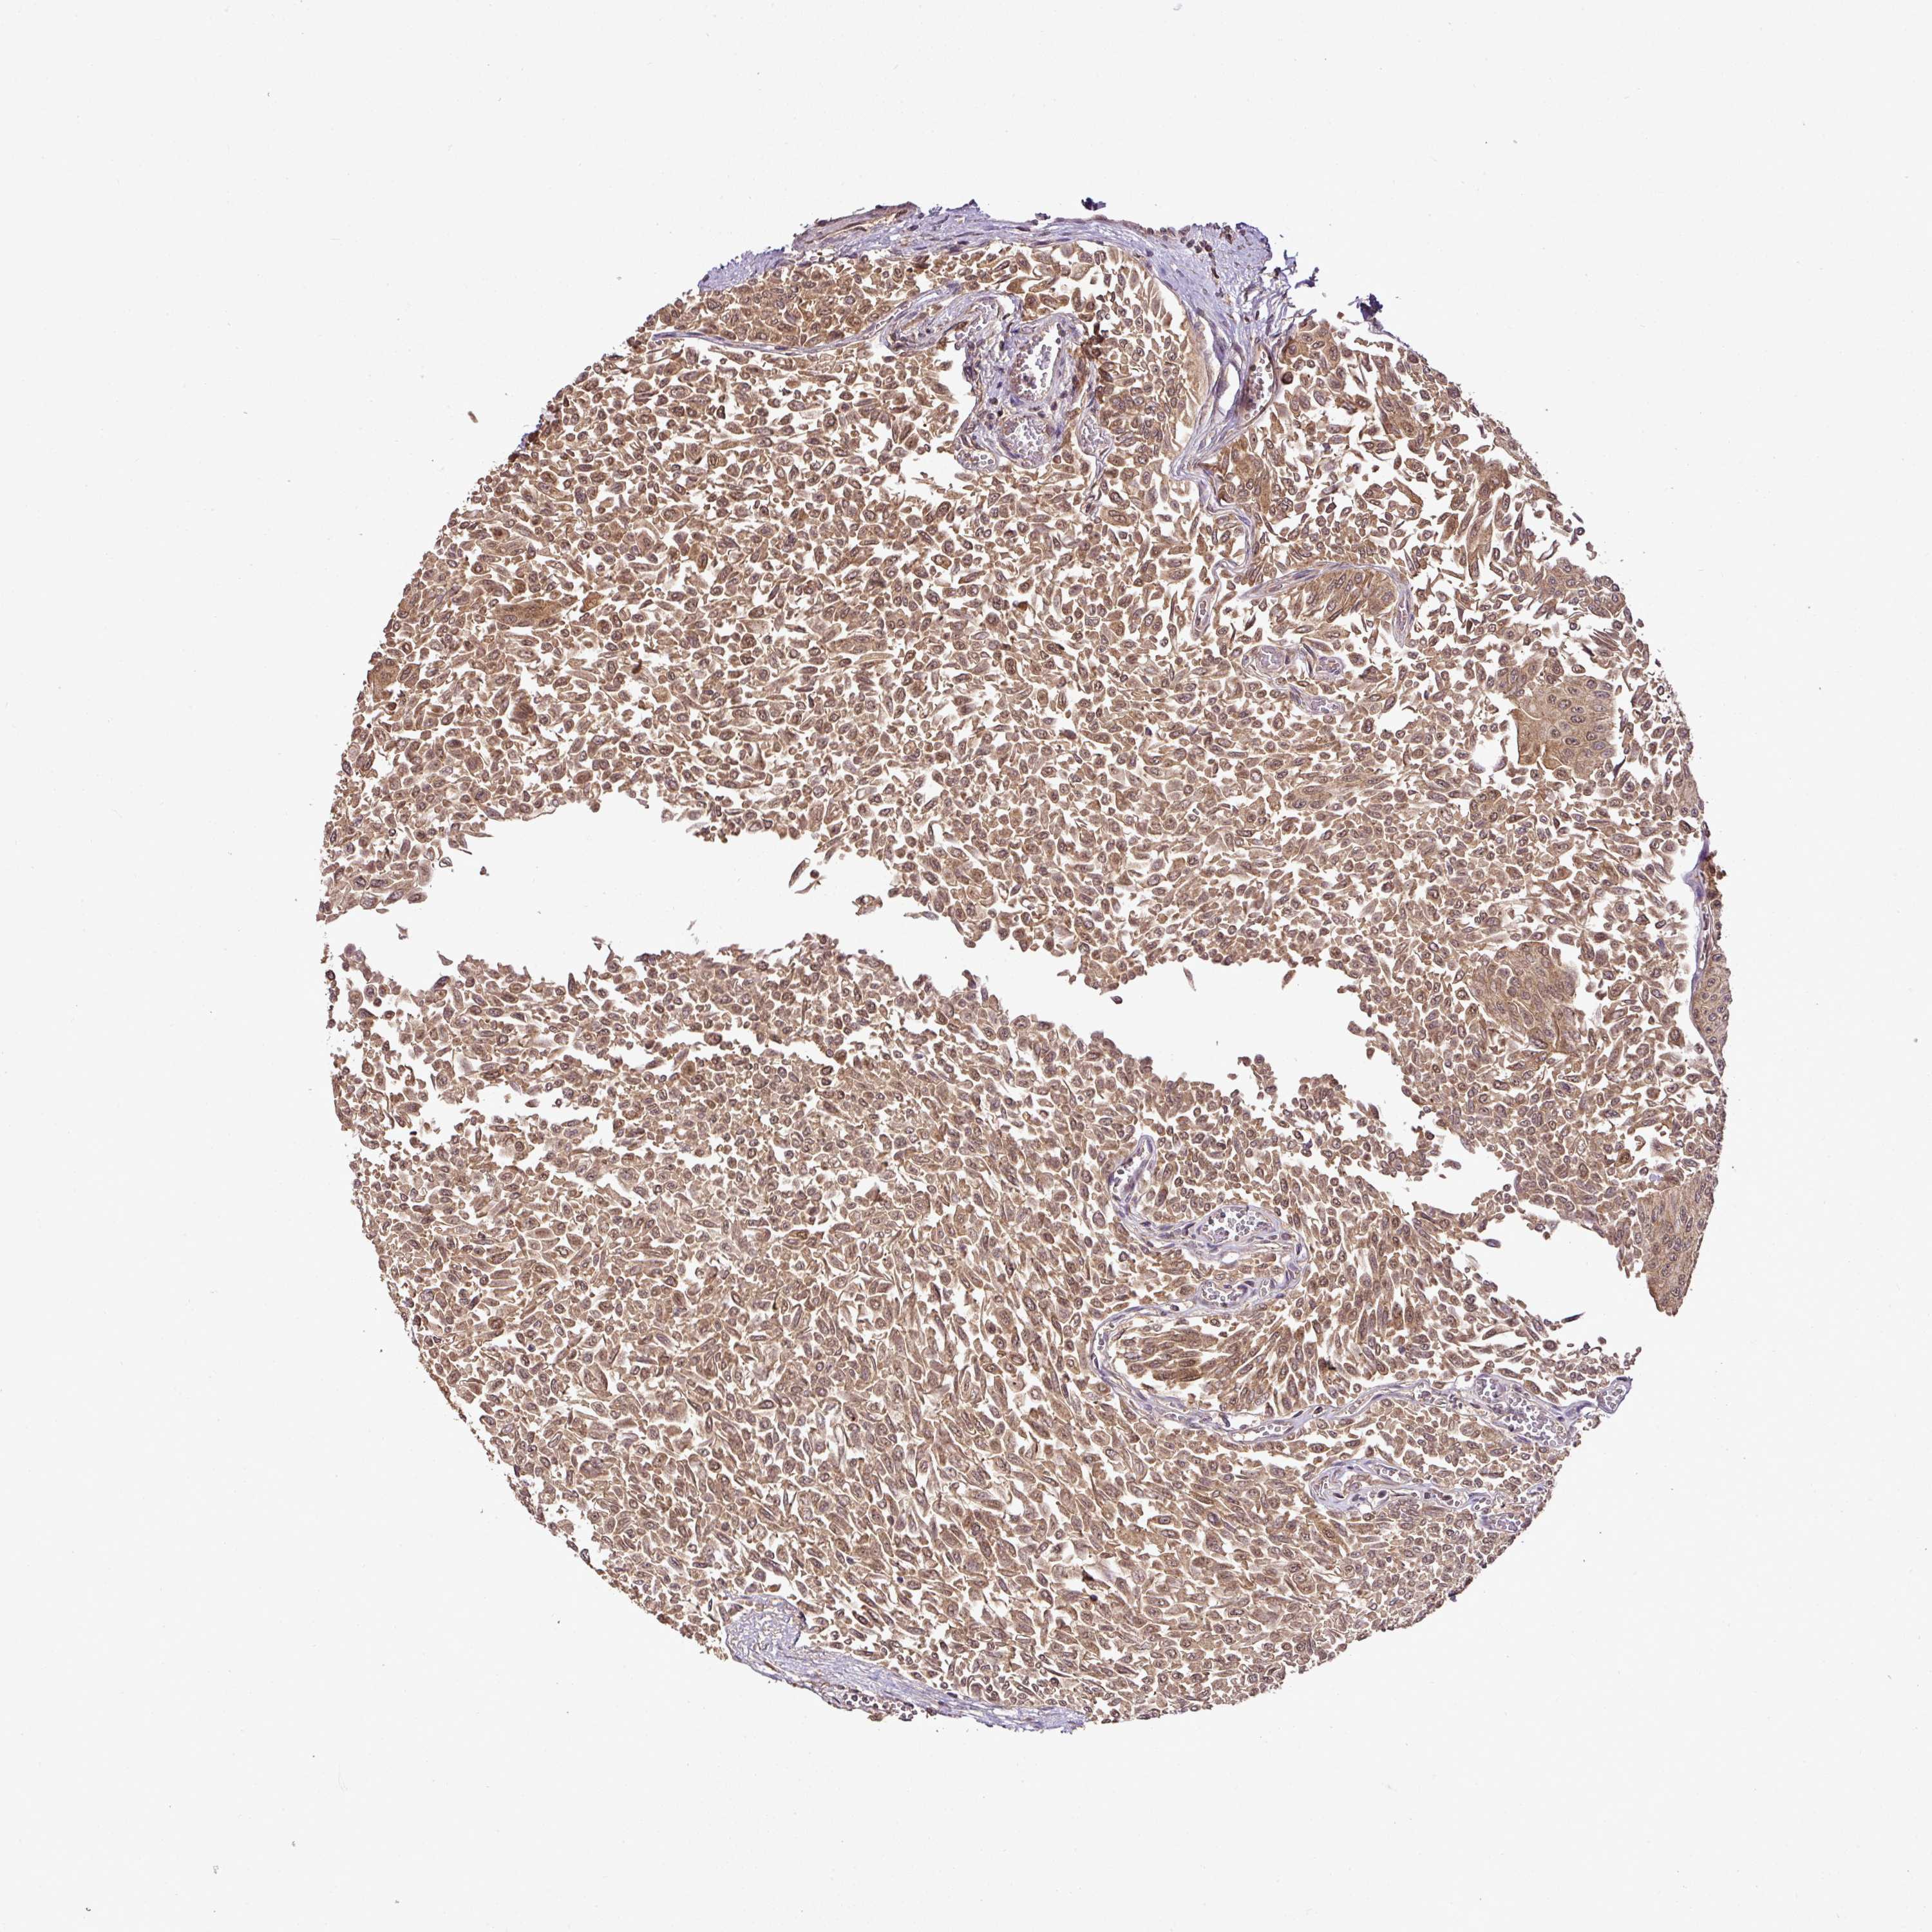

UROTHELIAL CANCER - Protein expressioni

A mouse-over function shows sample information and annotation data. Click on an image to view it in a full screen mode. Samples can be filtered based on level of antibody staining by selecting one or several of the following categories: high, medium, low and not detected. The assay and annotation is described here.

Note that samples used for immunohistochemistry by the Human Protein Atlas do not correspond to samples in the TCGA dataset.

Antibody stainingi

Antibody staining in the annotated cell types in the current human tissue is reported as not detected, low, medium, or high, based on conventional immunohistochemistry profiling in selected tissues. This score is based on the combination of the staining intensity and fraction of stained cells.

Each image is clickable and will lead to virtual microscopy that enables deeper exploration of all samples and also displays staining intensity scores, fraction scores and subcellular localization as well as patient and tissue information for each sample.

Antibody HPA042440

Antibody HPA052209

Staining

High

Medium

Low

Not detected

Intensity

Strong

Moderate

Weak

Negative

Quantity

>75%

75%-25%

<25%

None

Location

Nuclear

Cytoplasmic/membranous

Cytoplasmic/membranous,nuclear

Urothelial carcinoma, Low grade

Urothelial carcinoma, High grade

Urothelial carcinoma, NOS